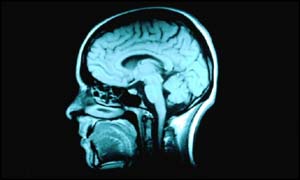

| Wednesday, 31 July, 2002, 18:04 GMT 19:04 UK Ultrasound hope for brain diseases  The technique is being developed in the US Doctors believe they have found a way of treating patients with serious brain diseases without the need for surgery. Researchers in the United States have suggested that sound waves could play a key role in helping to get drugs into the brain. They also believe their findings could be used to advance gene therapy and to help people with diseases ranging from cancer to Parkinson's.

This is because drugs cannot enter the brain via the bloodstream. A protective layer around the brain - the so-called blood-brain barrier - prevents drugs and other substances from passing into the brain. But Dr Ferenc Jolesz and colleagues at Brigham and Women's Hospital in Boston believe ultrasound could be used to overcome this problem. Shockwaves They have found a way to temporarily open the barrier to allow drugs and genes to be delivered into specific parts of the brain. They injected tiny protein bubbles into the bloodstream of three rabbits. These bubbles are widely used already to enable doctors to boost ultrasound images of blood vessels. But Dr Jolesz has discovered that bursting these bubbles can temporarily open the blood-brain barrier. He used an ultrasound beam to burst the bubbles in a specific part of the rabbit. This sent a shockwave up to the blood-brain barrier. This shockwave was found to be strong enough to allow large particles to get into the brain. According to New Scientist magazine, the doctors believe the technique could one day be used to help to deliver drugs and genes to the brain. These could include powerful drugs to kill off tumours or genes to restore damaged cells. However, they have warned that much more research is needed. Promising results Dr Christopher Newman of the University of Sheffield welcomed the research. He said the results were promising not least because ultrasound is safe. "I think it has a great deal of promise," he told the magazine. Professor Richard Mulligan of Harvard Medical School also hailed the findings and suggested they could be used to help patients with a variety of diseases. "Applications could include the treatment of cancer and different neurodegenerative diseases," he said. | See also: 15 Jun 00 | Health 22 Nov 01 | Health 31 Mar 99 | Health Internet links: The BBC is not responsible for the content of external internet sites Top Health stories now: Links to more Health stories are at the foot of the page. | |||||||||||||||||||||||||||||||||||||||||||||||||||||||||||||||||||||||||||||||||||||||||||||||||||||||||||||||||||||||||||||||||||||||||||